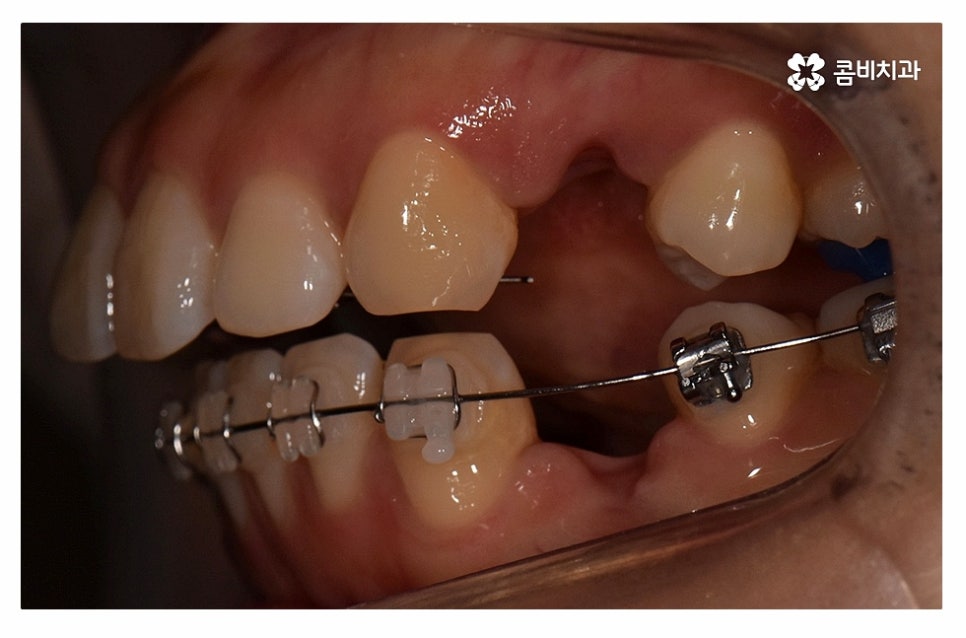

치아의 이동 공간 확보를 위해 발치 교정을 진행한 사례라고 할 수 있어요.

윗니는 설측교정으로 진행하고 아랫니는 일반적인 순측교정으로

치료를 진행하는 방식을 콤비교정이라고 부르고 있는데요.

콤비교정은 심미적인 치료 방법이며 혀가 위치한 아랫니는

순측교정을 하기 때문에 발음상의 불리함이나 이물감 등에서

유리하기 때문에 합리적인 치료 방법이라고 할 수 있어요.